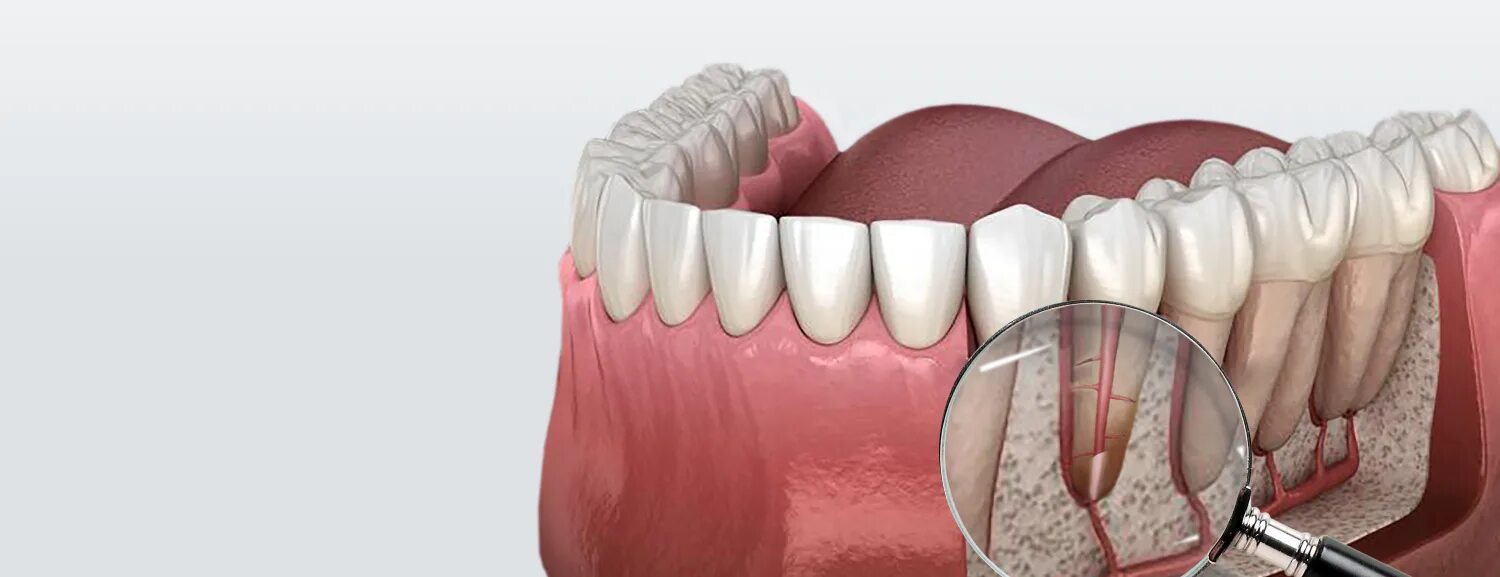

Ретроградное пломбирование корневых